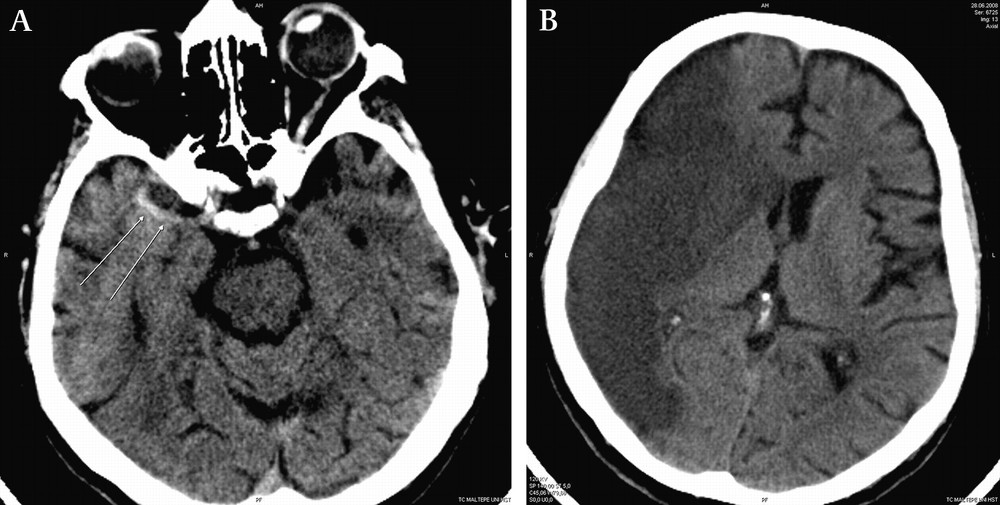

뇌출혈은 뇌 혈관이 파열되어서 발생하는 출혈을 의미합니다. 외상이나 심혈관 질환 등이 원인이 될 수 있습니다. 뇌출혈은 일반적으로 심각한 상태이며, 즉각적인 응급 조치가 필요합니다.

뇌경색은 뇌 혈관이 막혀서 일어나는 상황을 의미합니다. 이로 인해 뇌 조직이 손상을 입을 수 있습니다. "경색"이라는 용어는 혈액의 흐름이 차단되었다는 의미를 가지며, 이는 뇌의 영양을 공급하는 혈관에서 일어날 경우 심각한 문제를 초래할 수 있습니다.